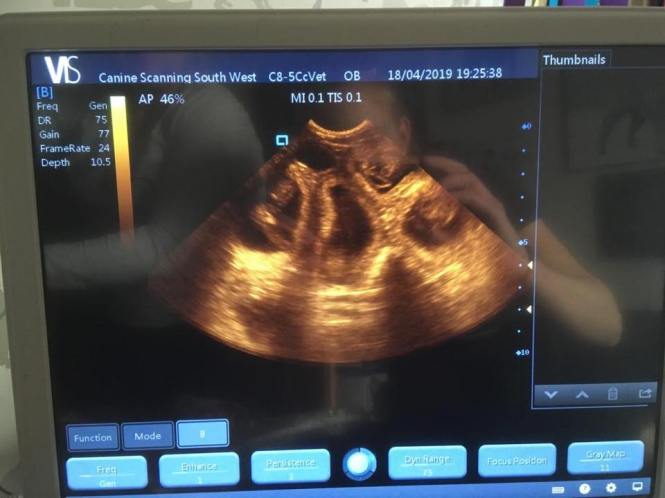

18-04-19

Elsa is pregnant!! We are very happy to announce that she is carrying a healthy looking litter inside of her. Exciting times!

UPDATE Elsa has been covered to Hank on the 17th and 19th of March

The F-litter is Avonwolf Born Free Elsa and Hank vom Brunsbeker Land.